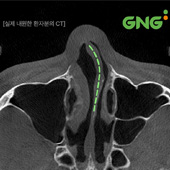

평소 비염, 코막힘 때문에 고민이신가요? 위 두 증상의 주요 원인은 무엇일까요? 심한 코막힘의 원인은 휘어진 비중격 연골에 있습니다. 본래 코 중앙에 수직으로 위치해 콧구멍을 둘로 나누는기둥 역할을 하는 비중격 연골이 휘어진 상태를비중격만곡증이라고 하는데요. 코막힘이 일시적이지 않거나 계절 또는 환경 변화와 상관없이 2주 이상 코가 막힌다면 변형된 코 내부 구조가 원인일 수 있습니다. 기류가 . . .

대한민국 코막힘 환자 중 약 70%는비중격만곡증을 가지고 있다는 사실,알고 계셨나요? 비중격만곡증이란코의 중앙을 나누면서 뼈와 연골로 이루어진비중격이 똑바르게 서있지 않고한쪽 또는 양쪽으로 휘어진 상태를 말합니다. 다른 질환도 마찬가지이지만,비중격만곡증 역시 복합적인 요인에 의해발생하기 때문에단순히 비중격의 모양을 확인하는 것만으로는정확한 원인을 단정 짓기 어렵습니다. ✅ 선천적으로 발생하는 . . .

GNG병원에는 대한민국 환자 2명 중 1명이비중격 교정술을 받기 위해 내원하는데요.그 이유를 아래에서 자세히 설명드리겠습니다.2023년 대한민국 병원급 의료기관에서코막힘 해결을 목적으로비중격 교정술을 받은 사람은 2,789명그 중 GNG병원에서 수술한 환자 수는1,570명으로 2명 중 1명인데요.이처럼 많은 환자분들이 찾고 있는 것을수치로 확인할 수 있습니다.1. 병원급 의료기관의료기관은 . . .